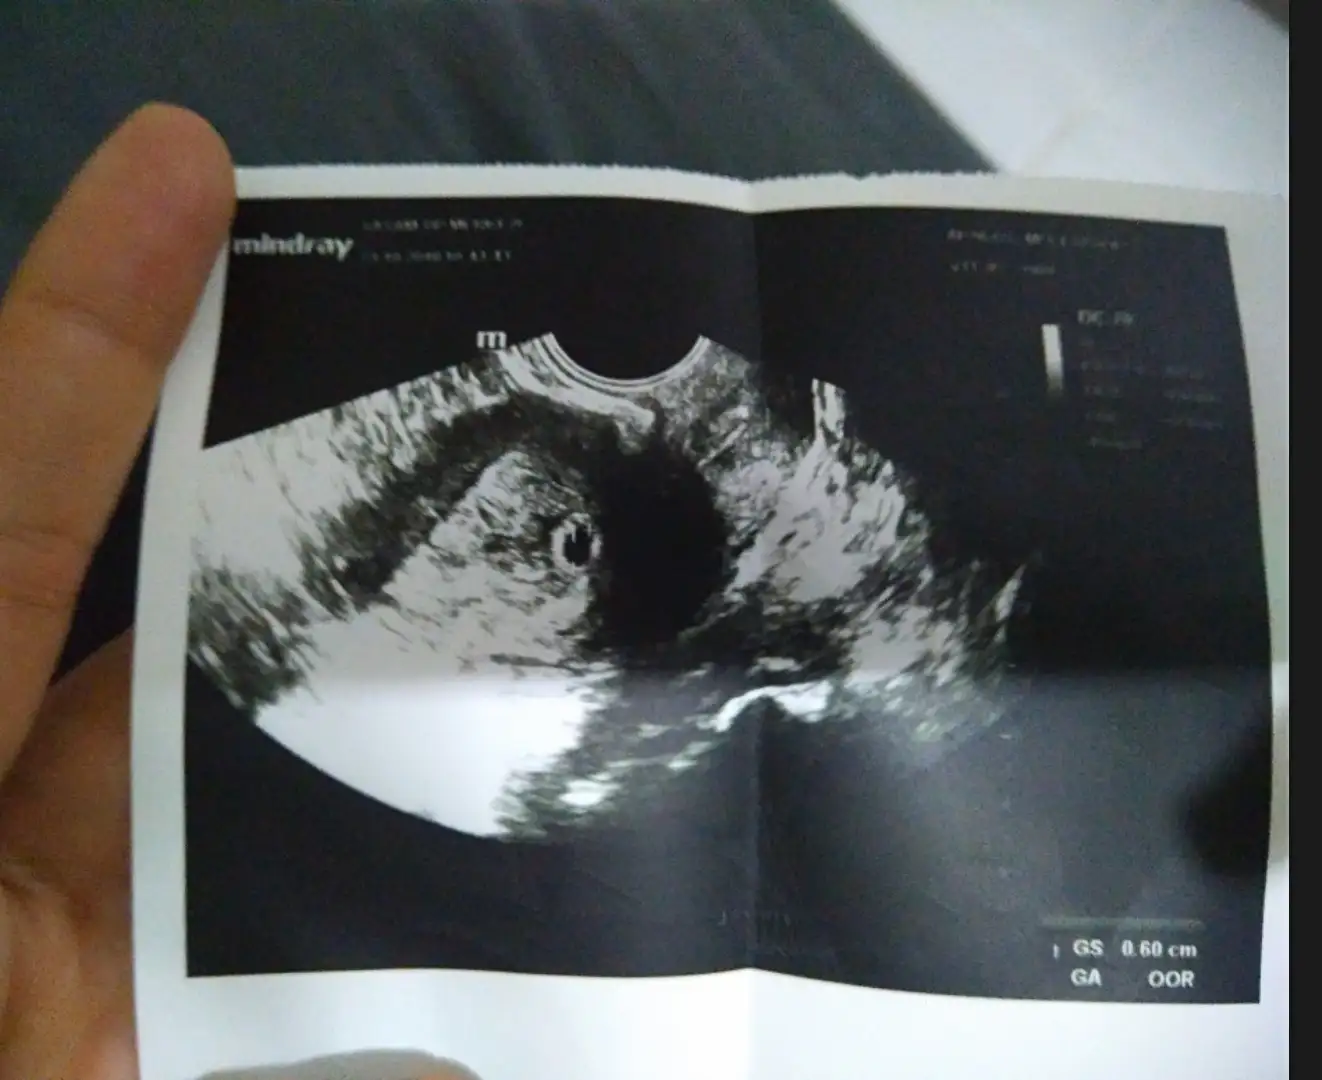

Amin kuzum benim darısı sana olsun inşallahYok kuzum usg goruntusunden bahsediyorum..:)

Amin sagol..Ultrason goruntusu yok mu yani:/Amin kuzum benim darısı sana olsun inşallah

yok kuzum vallaha en son kalbini dinletti vermedi kağıt sadece kese görüntüsü varAmin sagol..Ultrason goruntusu yok mu yani:/

Bebegi gorunce nasil vermedi yaa:/yok kuzum vallaha en son kalbini dinletti vermedi kağıt sadece kese görüntüsü var

sağda kesem :) bebişte sağdaymış öyle dediBebegi gorunce nasil vermedi yaa:/

şuan 7+4 11 haftalıkken ikili test yapıcam o zaman giderim ikiliden sonra gel dediMasallah simdi tam kac haftaliksin. Ne zaman kontrolun?